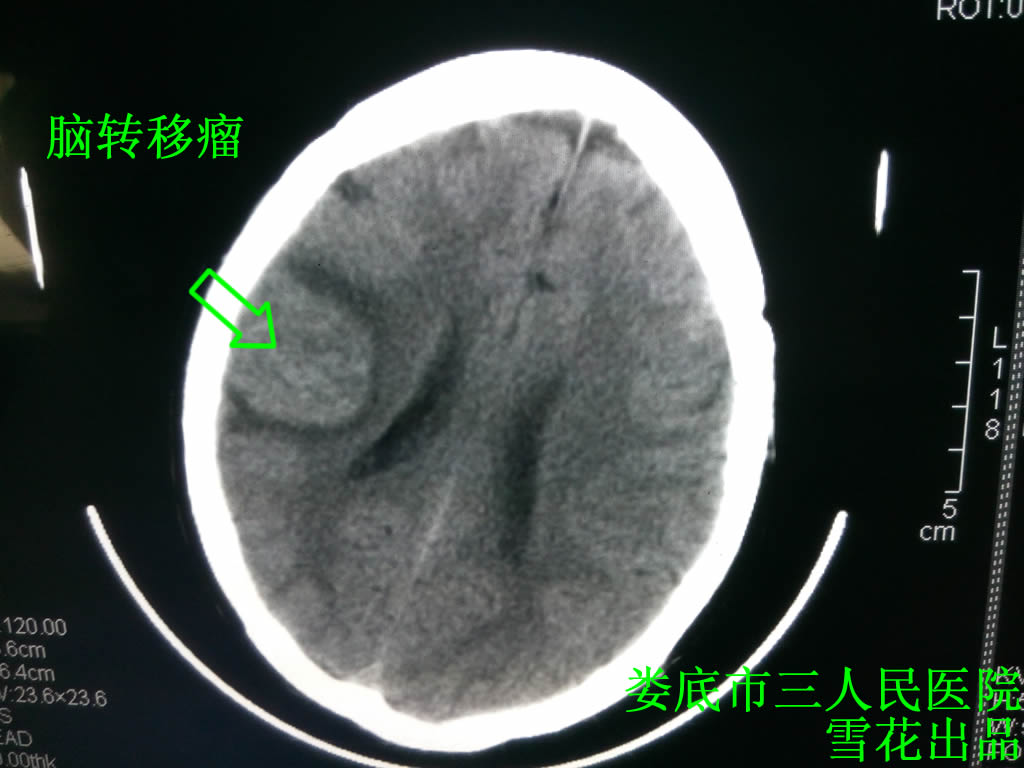

口服中药5剂后患者头痛有所好转,待取得患者一定的信任后,又多次建议患者行全颅放疗,患者终于答应,但要求放疗不能超过10次,给予全颅放疗30 Gy/10次,放疗后患者头痛明显好转,查头部CT示右额叶占位明显好转(见图三),但患者对治疗并不十分满意,因为放疗照射野区域的头发不断脱落,建议化疗,患者坚决拒绝,推荐试用靶向药物易瑞莎,(因患者拒绝基因检测,所有未行相关检查),口服易瑞莎1月后患者头痛消失,咳嗽也明显好转,查肺部CT示较前好转(见图四),建议患者坚持口服易瑞莎及中药,在之后的1年里患者一般情况良好,但1年后无明显诱因出现左侧肢体阵发性刺痛,查头部及肺部CT示较前无明显变化,照片及相关检查未见明显异常,结合临床仍考虑肺癌骨转移,因为患者拒绝放化疗,所以仅给予口服止痛药,治疗有效,现患者已追踪观察2年,头部及肺部病变未见复发。